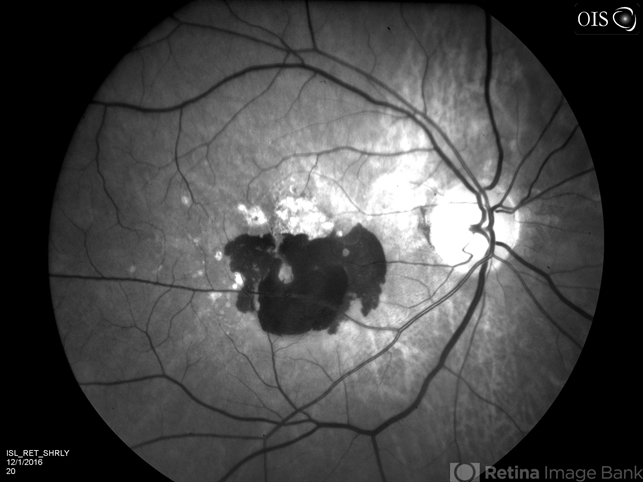

- hemorrhage, neovascular age-related macular degeneration (AMD), wet age-related macular degeneration (wet AMD), subretinal hemorrhage, red-free

- 89-year-old white male with NVAMD and new subretinal hemorrhage, red free photograph of the right eye. Currently receiving anti VEGF treatment.